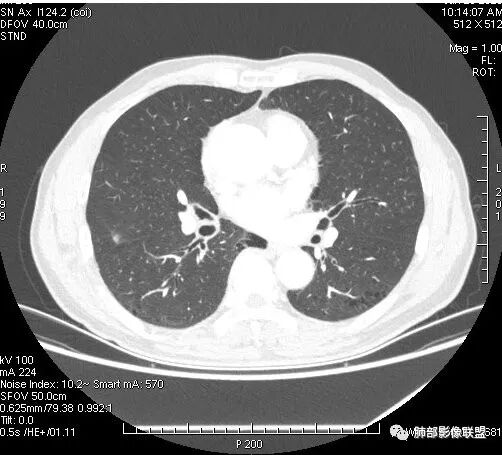

影像学改变:

1.右肺上叶后段类圆形结节影,密度不均,有坏死空洞,坏死比较彻底,内外壁都较清楚。

2.病灶有浅切迹,没有深分叶,毛刺大多细长且柔软。

3.可见棘状突起及胸膜牵拉,但未见胸膜凹陷。

什么意思?结节影有牵拉的动作,但似乎“出工不出力”,收缩力羸弱!

4.病灶轻到中度强化。病灶内血管走行较完好,病灶旁血管局部显示粗大。

5.支气管关系不确定。

6.灶周见小结节影(卫星灶),边界不甚清晰。